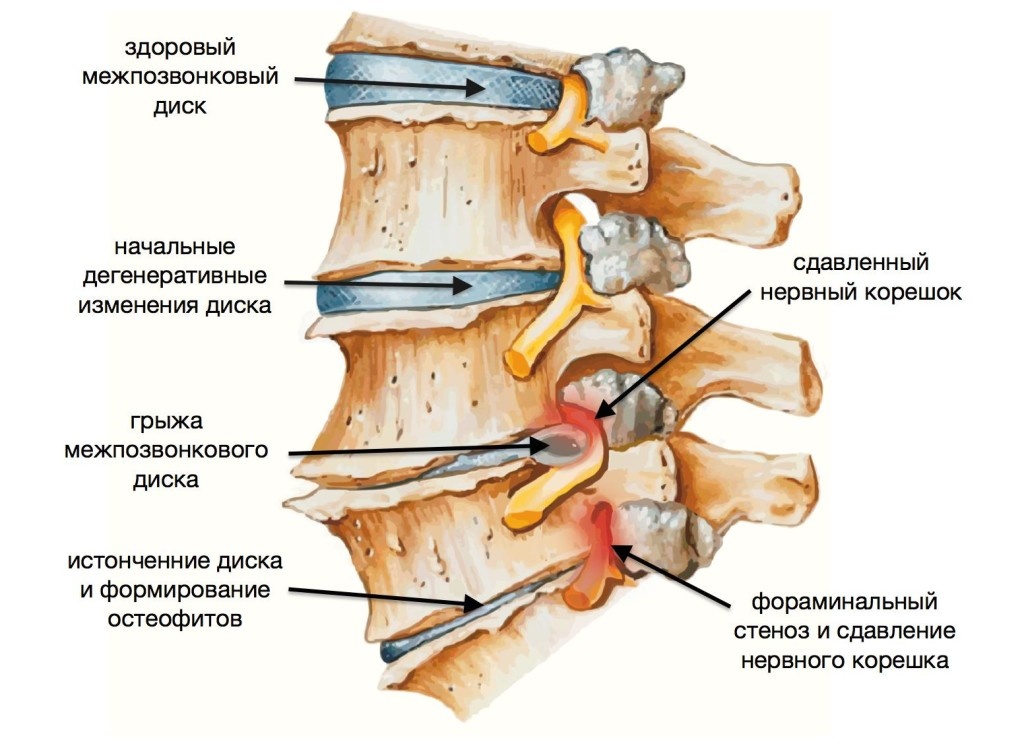

Остеоартрит фасеточных суставов: медицинские снимки и схемы